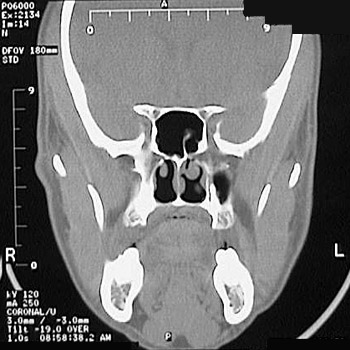

This is a normal sinus CT scan demonstrating the sphenoid sinus and nasal cavity and concha and maxilla and mandible in the skull.